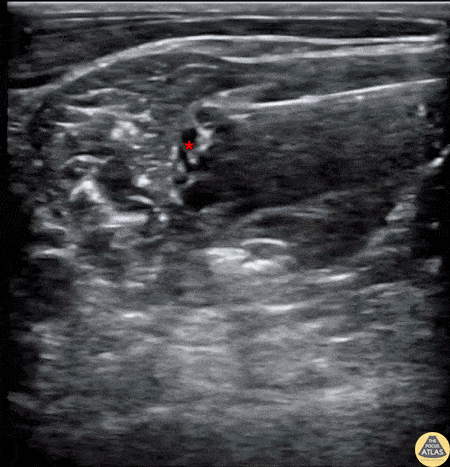

30s M with PMH of many previous shoulder dislocations presented to the ED with pain and reduced ROM of shoulder after lifting his arm slightly. Radiographs confirmed an anterior shoulder dislocation, so an interscalene brachial plexus nerve block was performed to facilitate closed reduction without the need for procedural sedation. The block is shown here, with the needle entering from the posterior/lateral aspect with the tip adjacent to the brachial plexus (*), just posterior to the anterior scalene muscle which is seen at the left of the image. The block was effective, and the shoulder was reduced without need for additional medications. Dr. Fred Milgrim, PGY3 Mount Sinai Emergency Medicine Residency